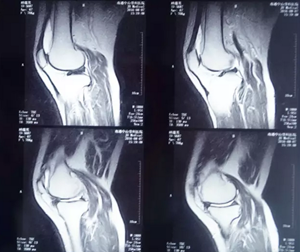

来到医院后,医生立马对顾女士进行检查,诊断为:双膝关节骨性关节炎,右膝关节半月板损伤。需要手术治疗。第二天,医师陆建玉又来到病房,告知顾女士和她的女儿手术的方案和各种手术方案的优缺点,充分理解后,选择手术“双侧膝关节镜检查+半月板修整术”。

8月10号,顾女士被推进手术室进行了“双侧膝关节镜检查+半月板修整术”,由胡玉华院长,李龙付副主任为患者手术。患者麻醉成功后,右大腿气囊止血带计时止血。台下连接关节镜各连接线,准备好关节镜手术相关设备。先在右膝钱髌韧带两侧各做一长约0.5cm切口,用血管钳分离至关节囊后用钝头穿刺器插入关节腔,放入关节镜,打开冲洗开关后观察膝关节……右膝手术结束后,对左膝同样进行手术,3个小时后,手术顺利完成了。